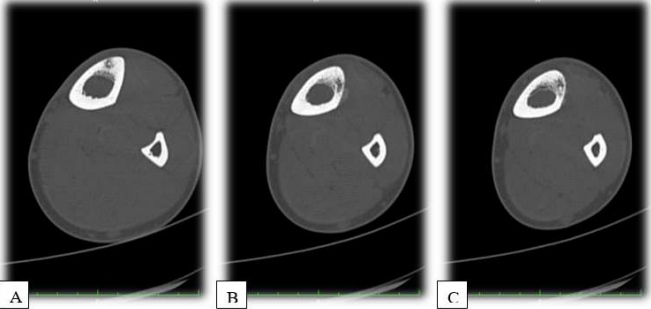

The following day, the patient underwent radiofrequency ablation (RFA) under CT guidance for osteoid osteomas in the left tibia, accompanied by a biopsy. The procedure was complicated by 2nd-degree burns at one of the ablation sites, which were later managed by plastic surgery. During the follow-up, wound cultures from the skin lesions tested positive for S. aureus. No other complications were encountered. Histopathology of the left tibial lesion biopsy revealed thickened trabeculae of bone with adjacent loose fibrovascular stroma and prominent osteoblastic rimming, which was consistent with OO. Postoperative radiographs were taken, and they demonstreated no abnormalities (Figure 7). During the follow-up examination, another bone scan (Figure 8) was performed after the operation. A tiny focal area of abnormal tracer uptake was observed involving the frontal bone along the lateral aspect of the right orbit, which is suggestive of a frontal bone osteoid osteoma.

Figure 7: Postoperative X-rays. (A) AP X-ray of the left tibia showing resolution of the cortical sclerosis and periosteal reaction at the midshaft region. (B) AP X-ray of the left tibia demonstrating normal bony architecture with no signs of the previous osteoid osteoma. (C) Lateral X-ray of the left tibia showing the absence of the previously noted cortical lesions and confirming successful treatment with no recurrence.